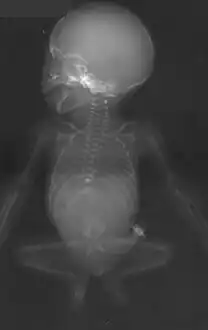

Antero-posterior radiographic view, showing missing ribs, absent lumbosacral vertebrae, hypoplastic pelvis and "frog-like" position of the lower extremities